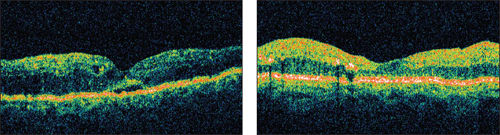

Figure 3. Pretreatment (left) and post-treatment OCT (right).